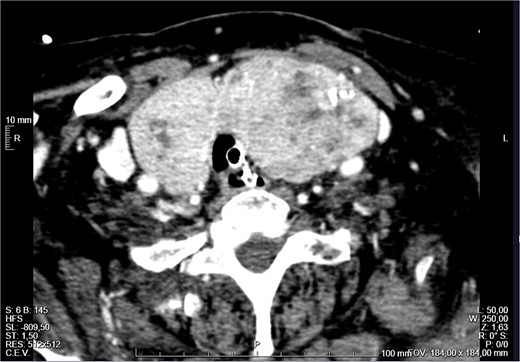

The patient remained monitored but a few hours later progressed with stridor and aggravated hypoxemia. An urgent nasopharyngoscopy was performed which showed significant laryngeal oedema and bulging of the posterior wall of the left hypopharynx. Despite systemic corticoid therapy, a decreased level of consciousness and desaturation lead to an orotracheal intubation. An urgent neck CT revealed a large multinodular goitre (RL 46 × 36 × 91 mm and LL 48 × 51 × 103 mm), with the superior pole of the left lobe ascending to the angle of the mandible, in a suprahyoid position, posterior to the submandibular gland (Fig. 1). The thyroid was extrinsically compressing the trachea and larynx, causing a deviation of the respiratory column to the right and narrowing of its lumen (Fig. 2). There was no apparent invasion of adjacent structures.

Neck CT showing a large goitre with extension to the left angle of the mandible.